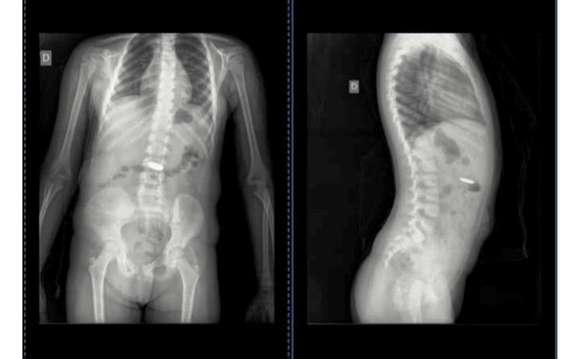

Una madre de Chascomús comunicó en redes sociales que debió consultar a 7 médicos para constatar que su hija se había tragado una pila